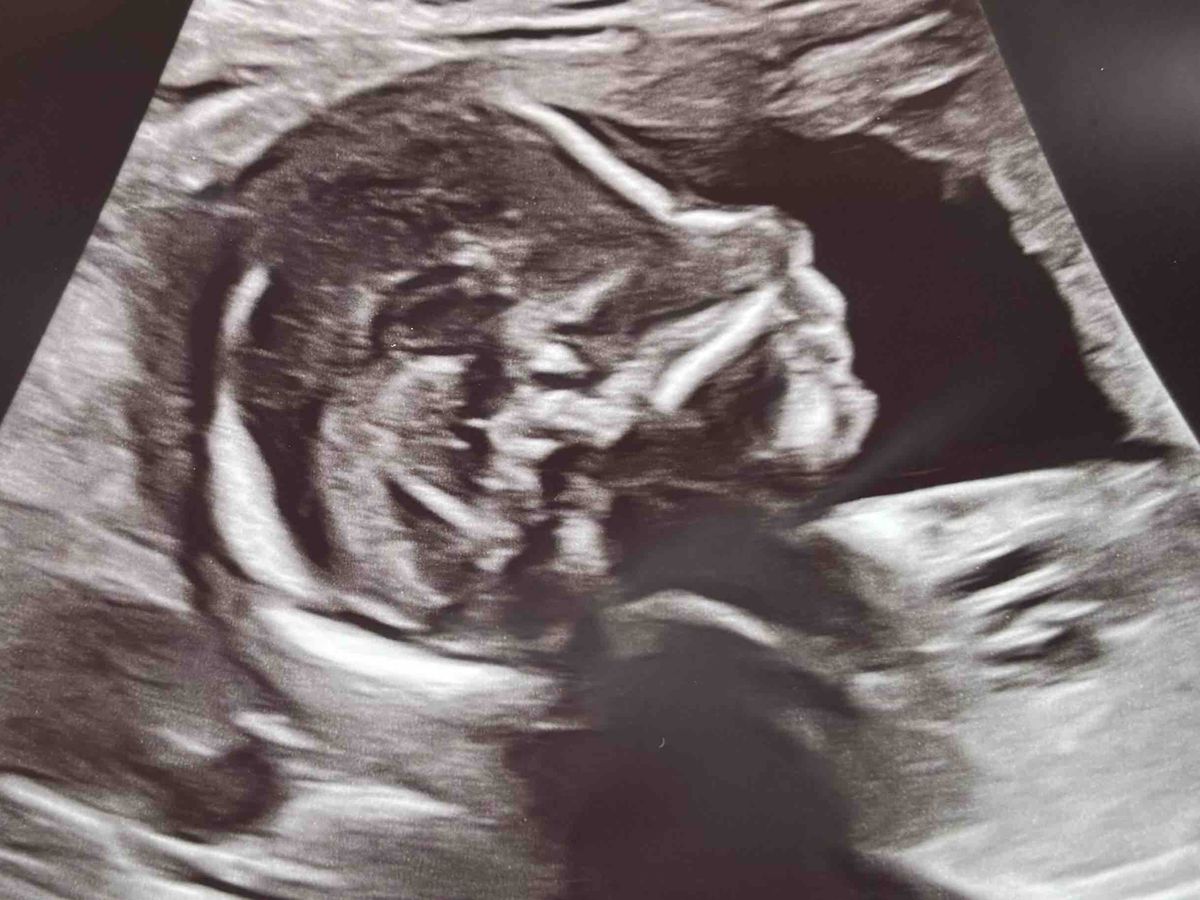

Hi everyone! We have been so excited to announce that we’re expecting a baby boy in May 2026, although I will admit this is not exactly the reveal we hoped for. What I originally expected to be the day I’d be getting ultrasound pictures we could use to announce our son to friends and family, quickly went the opposite direction as we were met with devastating news instead. I apologize in advance for the long reading ahead, but I want to be completely transparent and clarify exactly what is going on for our concerned friends and family!

During my scan, the doctor showed us that baby Christian has Spina-Bifida, as well as clubbed feet and some other birth defects going on. Spina-Bifida means the baby's spinal column doesn't close completely during early pregnancy, leaving the spinal cord and nerves exposed outside of his back. Due to the complexity of our situation, they referred me to Texas Children’s Hospital, which offers a surgery that can be performed during pregnancy to repair and close the opening on his spine. Spina-Bifida Fetoscope Surgery gives babies a better chance at independent walking, better leg function, and significantly reduces the need for brain shunts (hydrocephalus) compared to surgery after birth, by closing the spinal defect in-utero to protect the spinal cord from amniotic fluid damage, improving motor skills, and potentially reducing bladder/bowel issues.